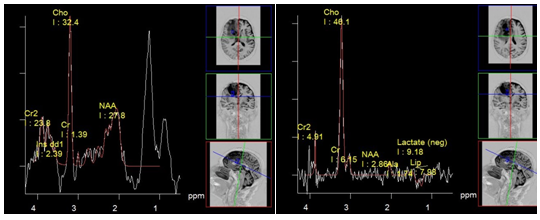

Ischemia: Ischemic stroke or infarction is an acute cerebrovascular accident due to a deficiency of arterial blood flow of the brain, leading to hypoxia and development areas of necrosis. It mainly develops due to occlusion of arterial vessels. The variation in metabolite profile over time gives valuable information for the diagnosis and prognosis of the disease. In the acute phase of infarction its core shows signs of anaerobic metabolism and cell death. Accordingly, spectra from the affected areas are characterized by a high lactate peak, often in combination with significant lipid peaks (Figure 3). Lactate in low concentrations, can also be detected in "penumbra", the area surrounding the core of ischemia. Lactate remains during few weeks the in the affected area.

Figure 3 Super acute infarction. PRESS, TE 30 ms (a) PRESS, TE 135 ms (b) marked decrease in NAA and myo-inositol. High lactate peak.

The slow decrease of NAA concentration in the affected tissue during several days, which can occur even weeks after onset, can't be explained only by destructive action of enzymes on NAA. So, it was suggested, that it is caused by ongoing Ischemia in the affected area. This also may explain the presence of lactate in the core of ischemia in the subacute phase.9 This has important diagnostic value for prognosis, and further treatment (Figure 4).

Figure 4 Infarction, sub acute phase. PRESS, TE 30 ms (a) TE 135 ms (b), lactate concentration map (c) and choline concentration map (d) marked decrease in NAA and myo-inositol (b), the high peaks of lactate and lipids. The map shows that the maximum concentrations of lactate and choline coincide topographically.